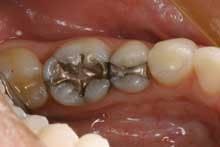

This patient is typical of our patients. She requested to have all the work in this quadrant completed at one time. The final result is a quadrant of posterior restorations that will last a long time and has improved the function and aesthetics of her teeth (Figure 2).

The benefit to the practice is important as well. We are able to work more efficiently on three or four teeth all at once than if we gave in to the "crown of the year" club mentality that we dentists help perpetuate in our patients. Also, we all know that the quality of the restorations is just a little bit better when they are all done at once - we don't "nick" the adjacent tooth while prepping; the laboratory technician has the ability to create correct and accurate proximal contacts and emergence angles; the lab technician also has the ability to help us correct or refine the patient's occlusion at this time.